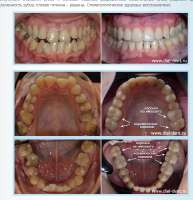

16953018548481.png 364Кб, 600x800

600x800

16973002837440.png 150Кб, 565x414

565x414

16988896475040.png 45Кб, 287x200

287x200

16968953426140.png 1563Кб, 1665x1250

1665x1250